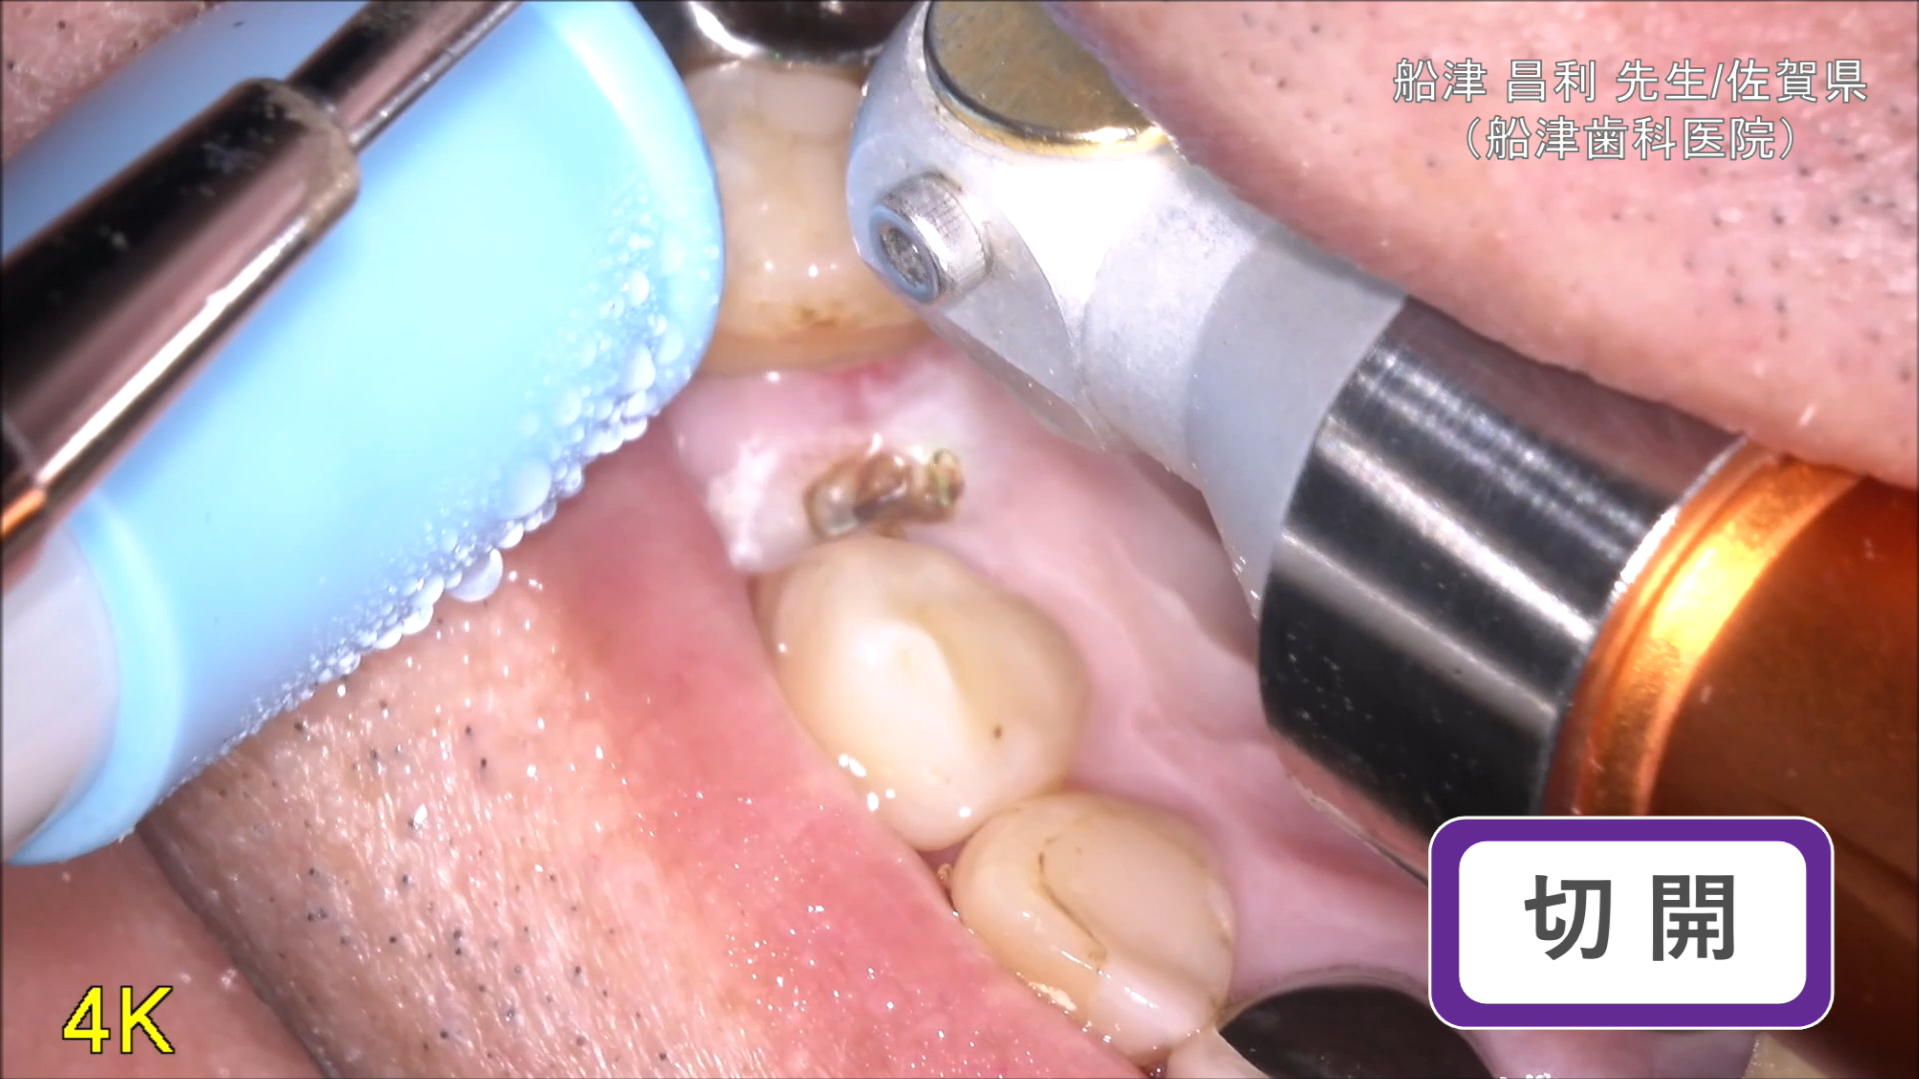

臨床例:注水型炭酸ガスレーザーNEOS(最大出力25W)を使用した先生の臨床例です。

切開